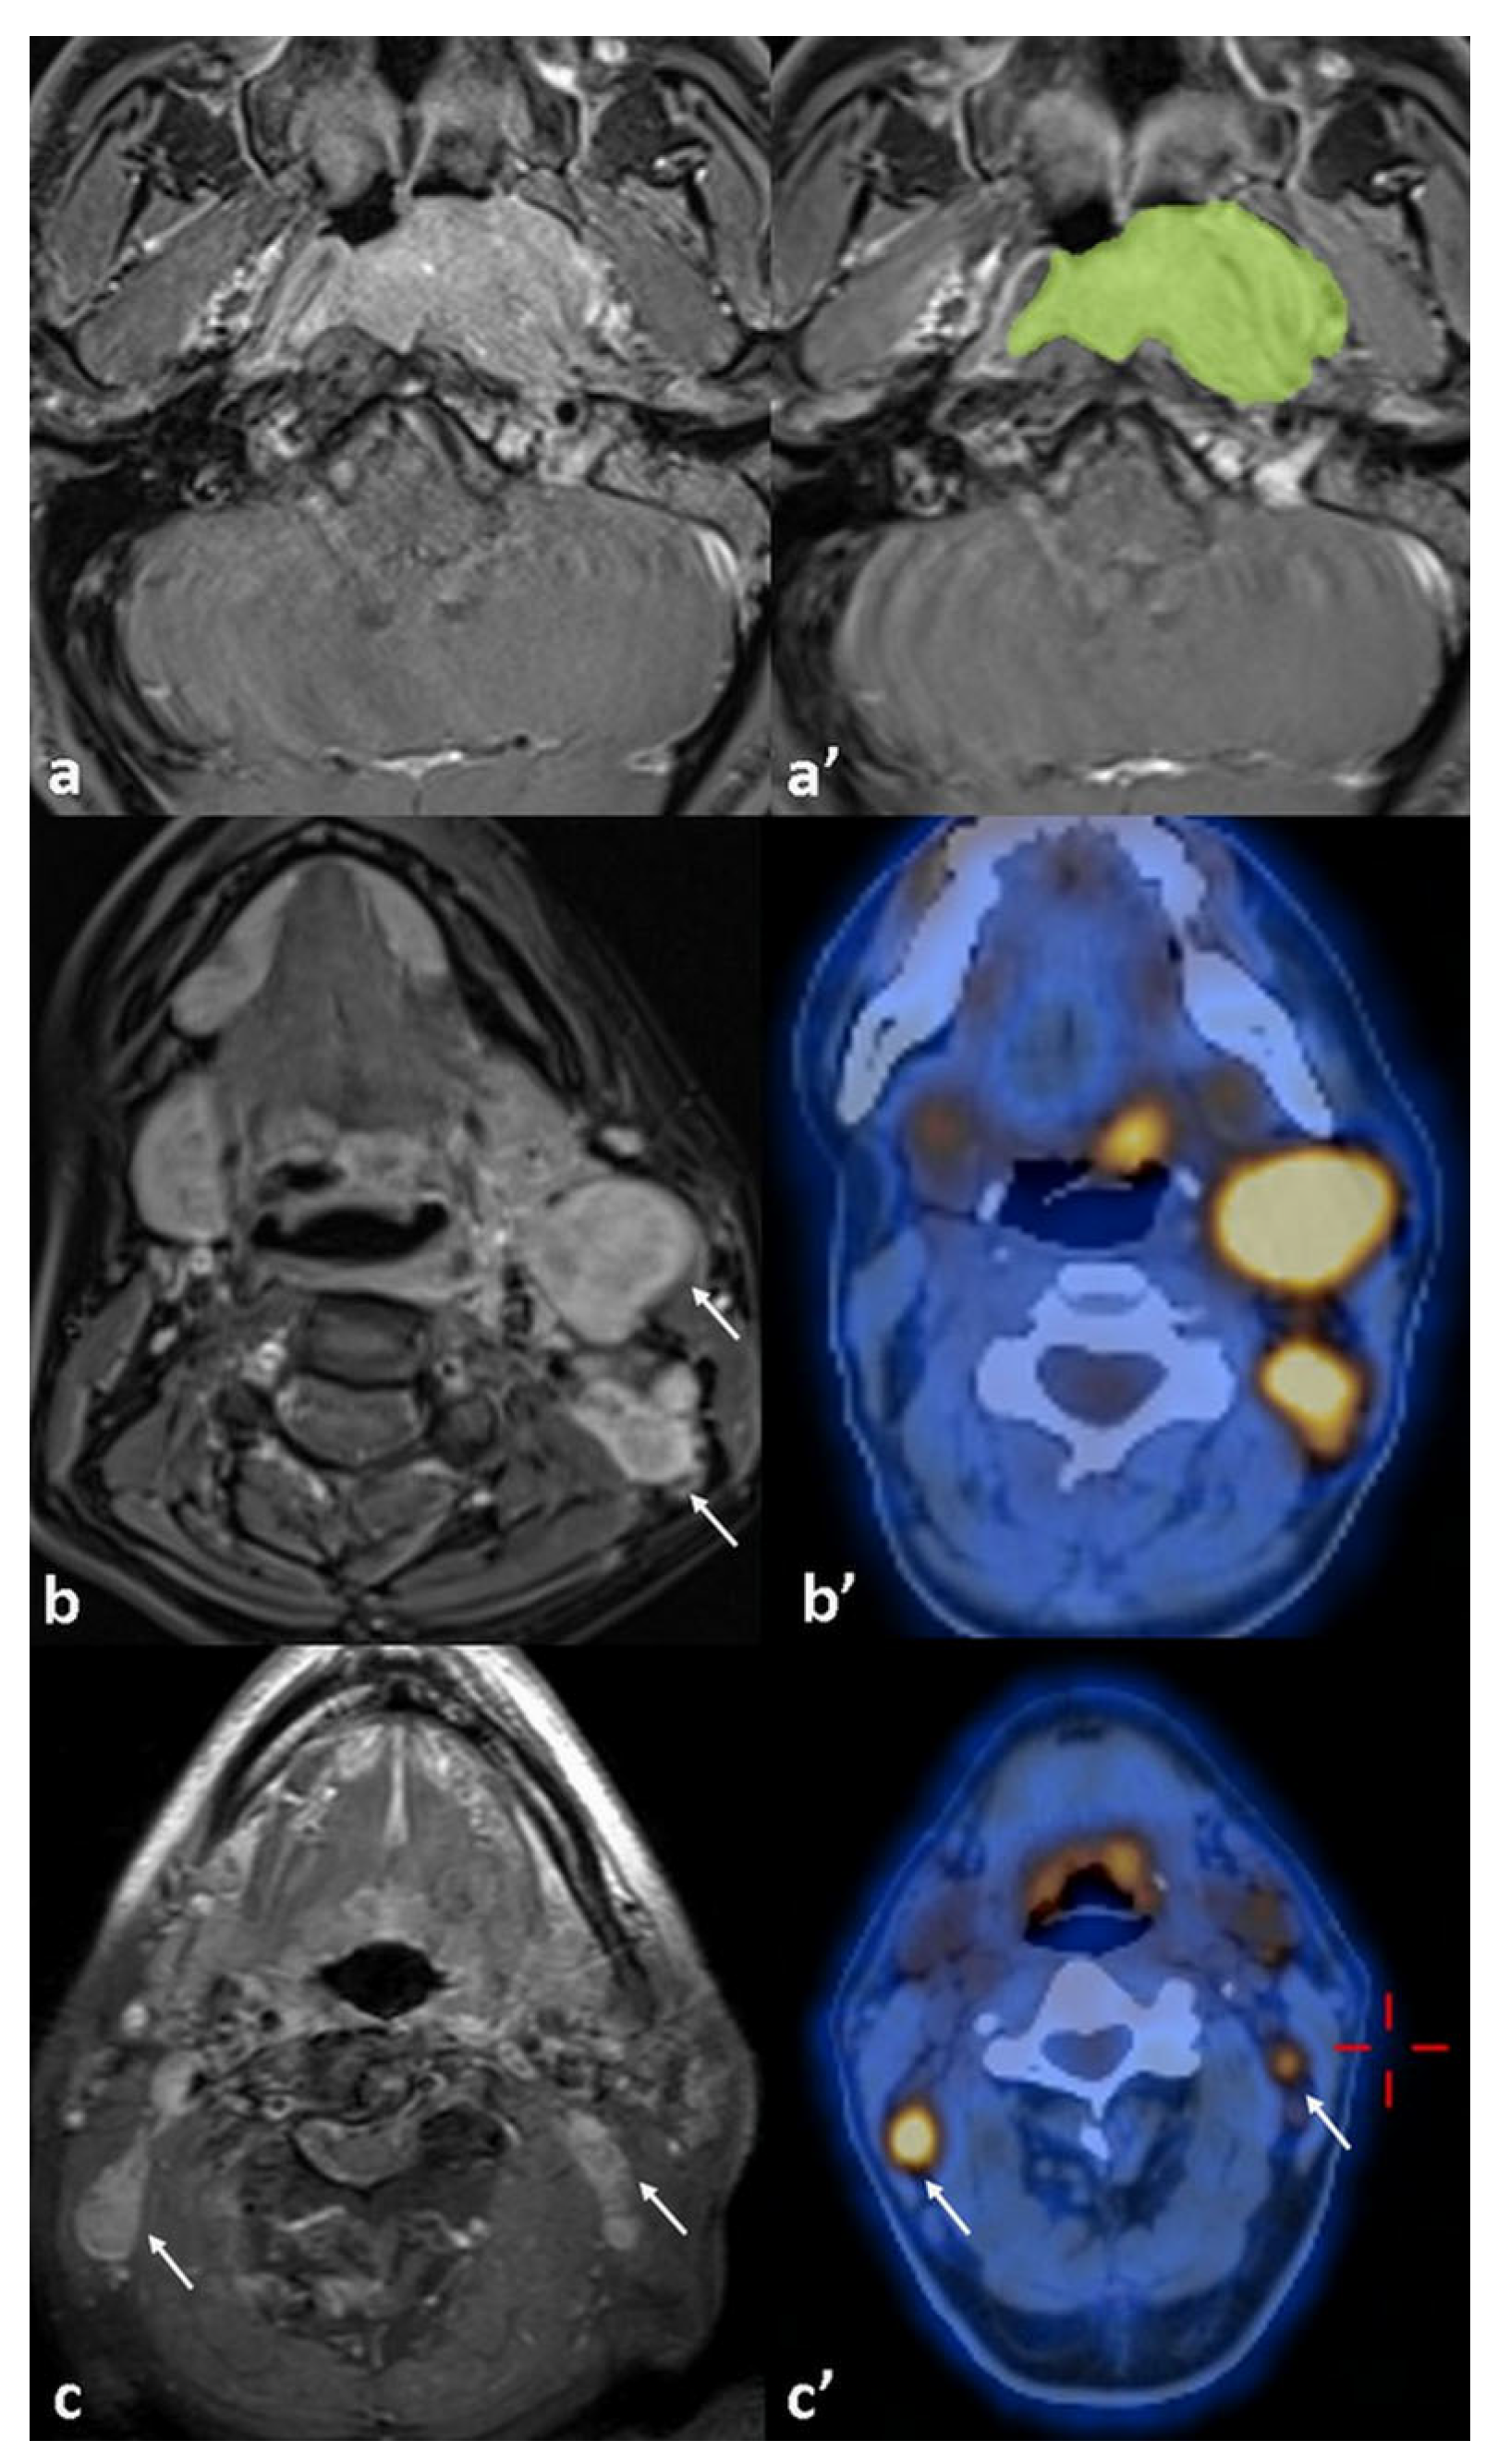

| GTV cm3 (mean) | 0.019 * | 0.042 * OR: 1.08 95%CI [1.02–1.16] | |

| No recurrence/recurrence | 11.6 (±1.6)/30.9 (±8.2) | ||

| 18FDG-PET/CT (PT) | 0.915 0.757 | ||

| MTV | 21.7 (±3.1)/42.2 (±11) | 0.049 * | |

| TLG | 164.4 (±27)/394.2 (±121) | 0.045 * | |

| SUV-max | 14.9 (±1.1)/15.9 (±2) | 0.328 | |

| SUV-mean | 6.8 (±0.4)/7.6 (0.7) | 0.195 | |

| SUV-peak | 12.2 (±0.9)/13.4 (±2) | 0.281 | |